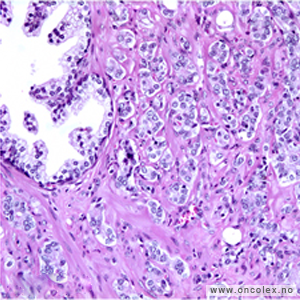

De fleste kreftsvulster i prostata er av en acinær (bærformet) type og kalles ofte bare prostatakarsinom. Vel 1% av prostatakarsinomene utgjøres av andre varianter som ofte har dårlig prognose (duktalt karsinom, mucinøst karsinom, signetringcellekarsinom og småcellet karsinom). 5% av krefttilfellene i prostata utgjøres av andre typer som utgår fra overgangsepitelet i urinrøret/pars prostatica urethra (urothelialt karsinom), støttevevet (sarkomer) eller lymfoid vev (lymfomer).

Bildeeksempler av vevsprøver

Gleasongraderinger

De mest aggressive svulstene har Gleasongrad 5, score 9–10 = ISUP 5. Gleason score (GS) angis for hver nålebiopsi som summen av den dominerende og sekundære grad. Den sekundære grad oppgis bare dersom den utgjør mer enn 5%.

Tertiær Gleasongrad 4 eller 5 rapporteres selv om de utgjør < 5%. Ved Gleasonscore 7b (4+3) er den dominerende Gleasongrad 4. Disse har dårligere prognose enn Gleasonscore 7a. Svulster med Gleasonscore 6 er lavgradig, Gleasonscore 7 er intermediære, mens Gleasonscore 8–10 er høygradige.

Aggressive svulster av typen duktalt karsinom, signetringcellekarsinom og småcellet karsinom graderes ikke.